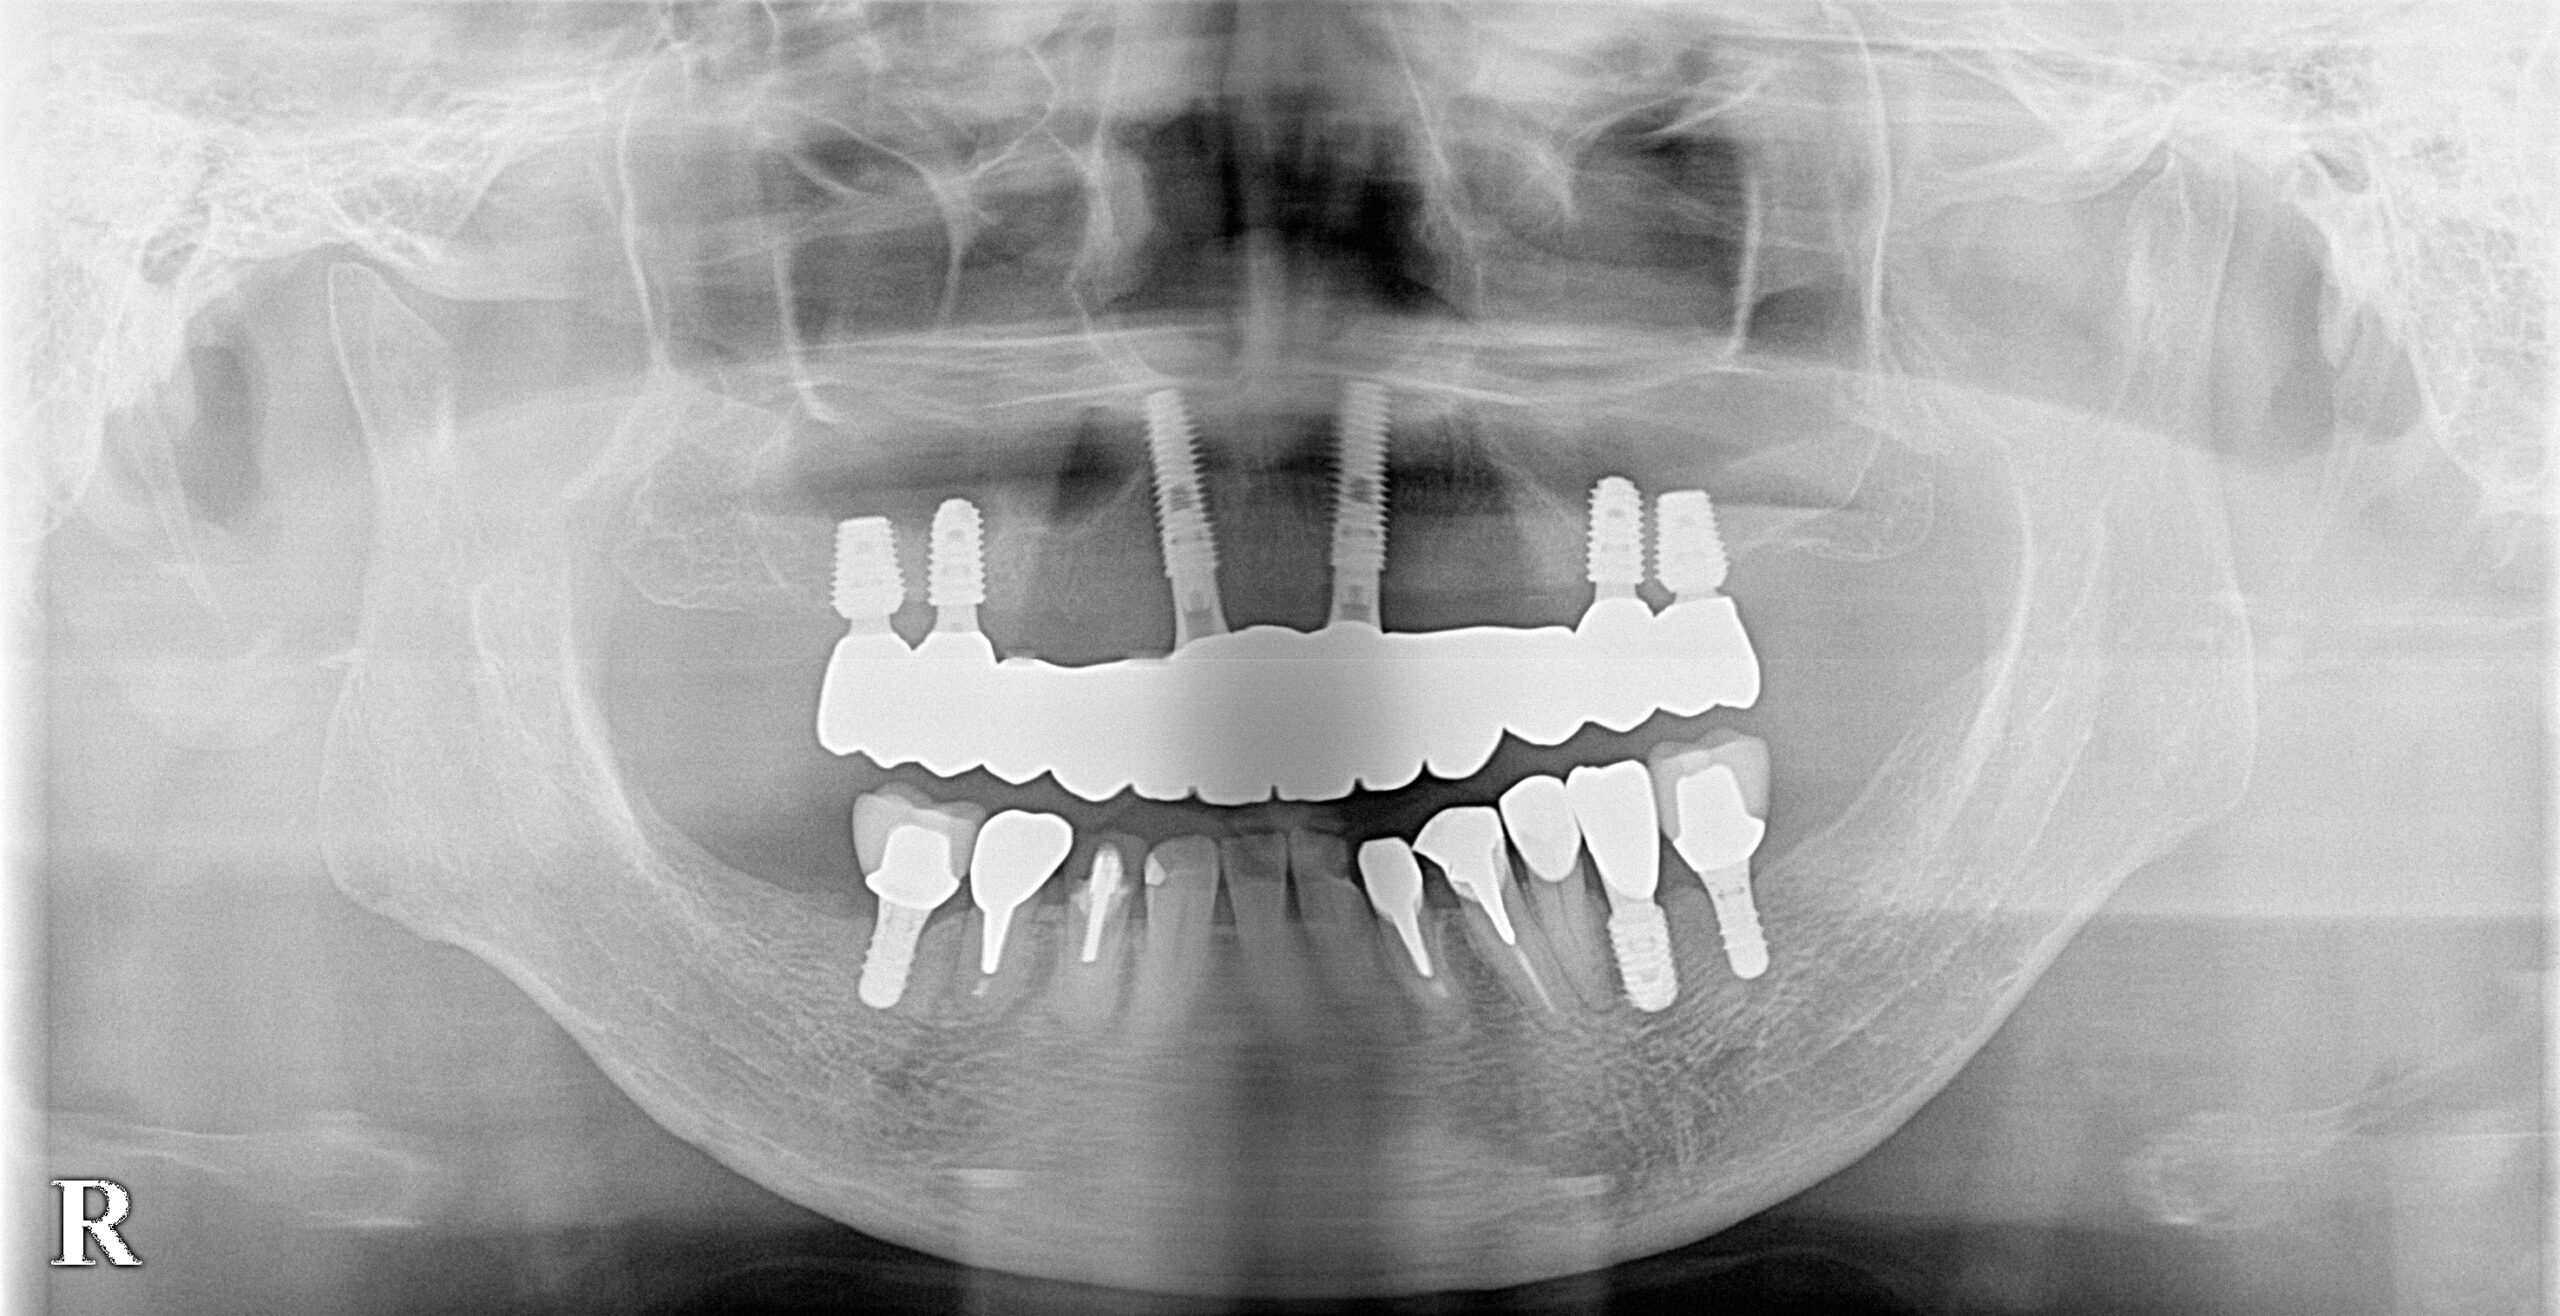

60代女性 AGC(全顎インプラント)

- AGC(全顎インプラント)治療

- 入れ歯を卒業したいと、全顎的なインプラント治療を決意されました。

- 特殊な「AGC構造」で作られるインプラントブリッジは、ネジも接着剤も使わず高精度の嵌合で固定されます。この患者様は6本で連結されており、簡単には外れませんが、専用器具で着脱可能です。丸洗いできるため衛生的で、将来的に介護が必要な場合も対応しやすいなどの特徴があります。